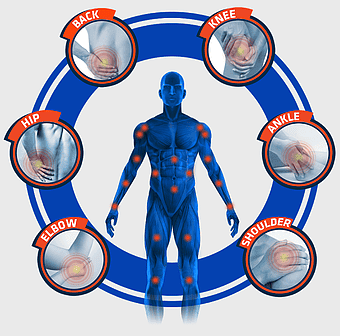

knee pain illustration, osteoarthritis joint pain, medical pain management, violet medical, skeletal joint health, chronic pain therapy, human anatomy injury -

orthopedic surgery, traumatology medicine, orthopaedics pathology, orthopedic therapy, skeletal health, joint treatment, spine care -

Knee pain management, arthritis joint therapy, human body musculoskeletal pain, low-level laser therapy for joints, osteoarthritis discomfort solutions, comprehensive joint health, systemic pain relief strategies -

rheumatoid arthritis illustration, chronic pain therapy, joint replacement surgery, blue violet human skeleton, skeletal anatomy diagram, arthritis pain relief methods, orthopedic health visual aids -

arthritis pain symptoms, rheumatoid arthritis illustration, joint pain areas, human body anatomy, skeletal health issues, medical visualization, chronic joint discomfort -